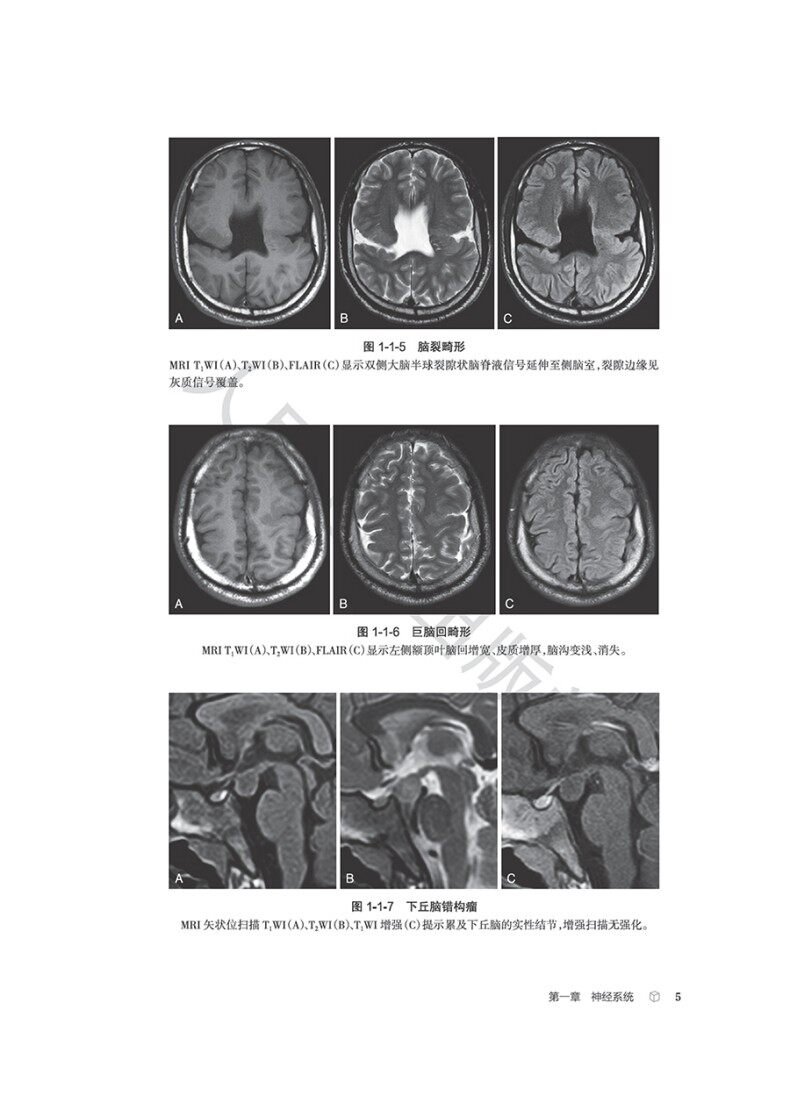

本书从影像科医师的日常工作出发,以中华医学会放射学分会青年学组的“青影智慧-影像诊断思维系列培训课程”内容为基础,系统梳理、收录神经系统、头颈与五官、呼吸系统、心脏和大血管、乳腺、消化系统、泌尿系统、生殖系统、骨关节等影像科日常工作中的近300个常见征象,从每个征象的分析入手,凝练影像征象的特征,辅以征象典型图进行说明,应用思维导图展现征象分析和诊断的思路,并融入鉴别诊断点和相应的疾病谱,抽丝剥茧,去伪存真,示范从影像征象到诊断疾病的思维过程。